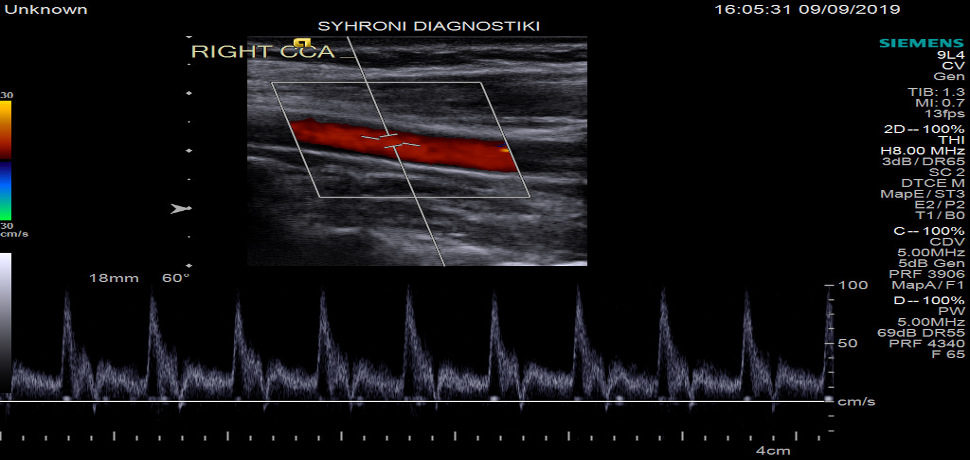

• Triplex Καρωτίδων και Σπονδυλικών Αρτηριών

Το triplex αγγείων χρησιμοποιεί ηχητικά κύματα (φαινόμενο Doppler) για την αξιολόγηση του κυκλοφορικού συστήματος του σώματος και συμβάλλει στον εντοπισμό αθηρωμτικών αλλοιώσεων / στενωσεων /αποφραξεων στις αρτηρίες και την ανίχνευση θρόμβων αίματος και ανεπαρκειας στις φλέβες. Δεν υπάρχει έκθεση του ατόμου σε ακτινοβολία και είναι τελείως ανώδυνη εξέταση.